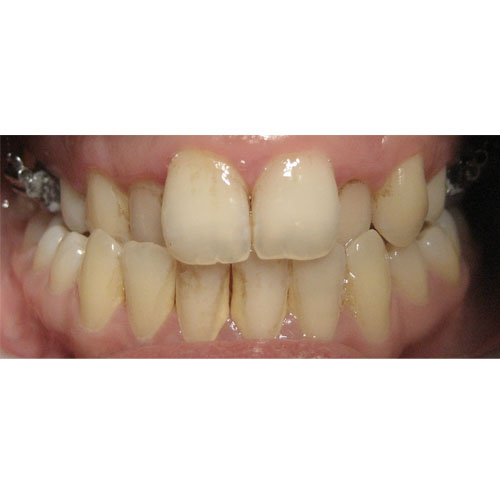

Nasze rezultaty